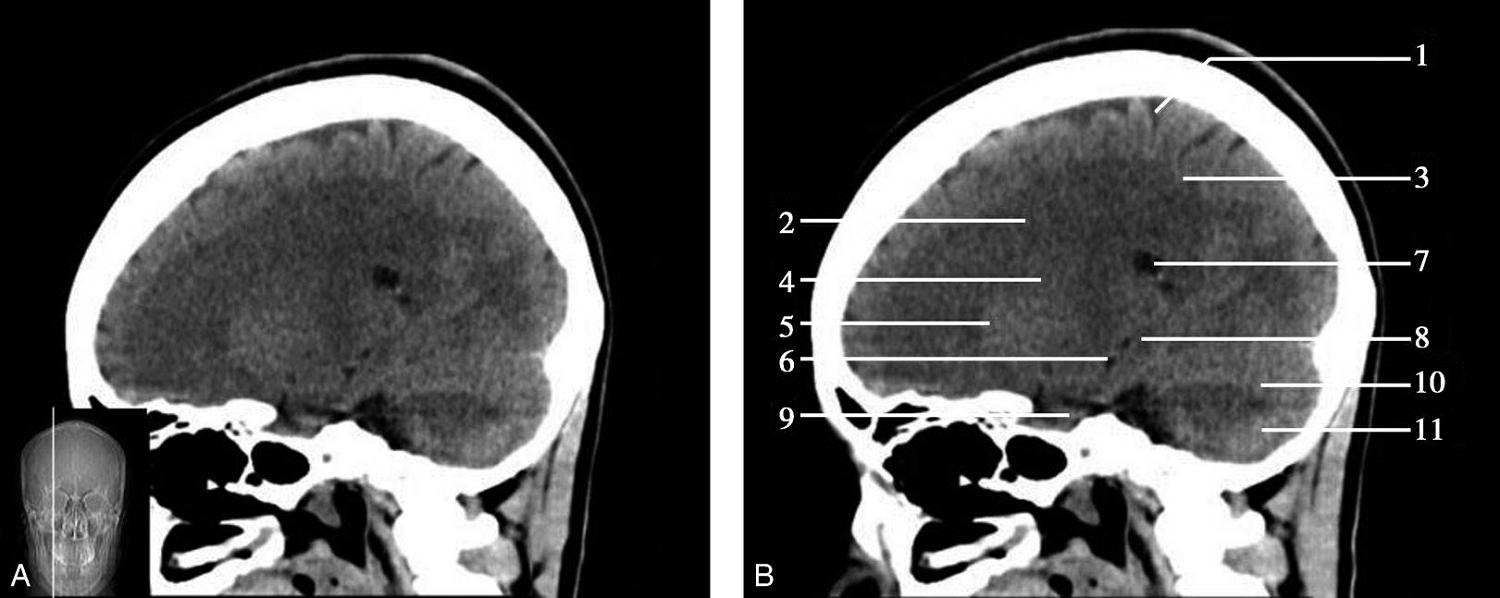

图1-2-59 正中矢状面CT

A.矢状面;B.矢状面标注

1.中央沟;2.扣带回;3.胼胝体体部;4.侧脑室;5.中脑;6.胼胝体膝部;7.穹隆;8.第三脑室;9.胼胝体压部;10.垂体;11.中脑导水管;12.第四脑室;13.脑桥;14.蝶窦;15.斜坡;16.小脑扁桃体;17.延髓

此层面可显示胼胝体全貌,它位于层面中央区域,是呈上凸下凹的弧形结构,由前向后分为嘴、膝、体和压四部分。扣带回环绕胼胝体上方,扣带沟位于扣带回的上方。大脑半球中部和后部分别可见较深且恒定的中央沟和顶枕沟。中央沟为是额叶顶叶分界标志。

胼胝体下方为侧脑室及穹窿,第三脑室借穹窿与前上方的侧脑室体部分开,背侧丘脑的内侧面以及中脑顶盖分别为第三脑室的外侧壁和底。第三脑室向前籍室间孔与侧脑室相通,向下经中脑导水管通第四脑室。中脑腔狭窄呈管状,即称为中脑导水管,中脑导水管畸形,常见者为导水管的分叉畸形和狭窄,其次可见中脑导水管膈膜,造成先天性脑积水。

脑干由中脑、脑桥和延髓组成,自第三脑室底向下后稍斜行,移行于颈髓。由上至下,脑干腹侧可见脚间池、桥前池和延髓池,脑干背侧可见大脑大静脉池、四叠体池和小脑延髓池。

垂体位于蝶鞍内,其前部为腺垂体,后上部分为神经垂体。垂体下方为鞍底及蝶窦,上缘因鞍膈存在而平直,垂体借垂体柄向上连于丘脑下部。垂体的前上方见视交叉和视束。斜坡作为前颅窝底的重要组成部分与多个重要结构相比邻,矢状位呈三角形,颅内肿瘤或颅外鼻咽部恶性肿瘤均可侵犯至此,原发肿瘤常见为脊索瘤。小脑幕居枕叶和小脑之间,向后下连接窦汇,向前至中脑后方游离,称小脑幕切迹。小脑幕下方为小脑扁桃体。成年人小脑扁桃体下缘由枕骨大孔向下疝入椎管超过5mm称为Chiari畸形,以矢状位显示最佳。